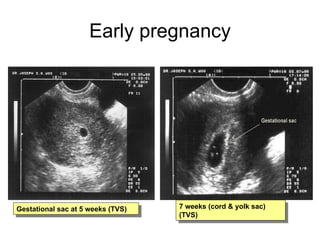

Early pregnancy Gestational sac at 5 weeks (TVS) 7 weeks (cord & yolk sac)   (TVS)

Early pregnancy Gestationalsac at 5 weeks (TVS) 7 weeks (cord & yolk sac) (TVS)